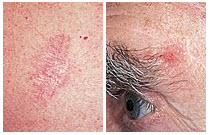

Basal Cell Carcinoma (BCC) Photos

A small pink growth with a slightly raised, rolled edge and a crusted indentation in the center. (BCC)